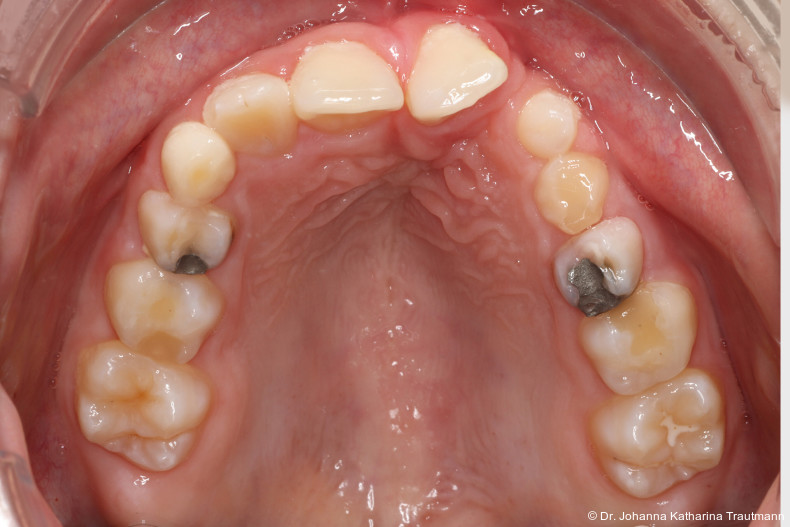

Das Fernröntgenseitenbild zeigte eine skelettale Klasse IIAnomalie mit einem Wits von 5,6 mm, bei einer tiefen Konfiguration (ML NL = 16,5°) mit bialveolär retrudierten Fronten (OK1NA = 5,9°; UK1NB = 10,4°), was sich auch in der Modellanalyse widerspiegelte. Hier zeigte sich zudem ein schmaler Oberkiefer mit multiplen Kippungen und Rotationen in der Front, einem hypoplastischem 22 sowie einer Mesialwanderung des 16. Des Weiteren zeigte sich eine asymmetrische Bisslage mit 1 PB distal rechts und ½ PB distal links bei einem Overjet von 2,5 mm sowie einem Overbite von 5 mm. Während im Unterkiefer bereits die zweite Zahnwechsel phase begonnen hatte, zeigte sich im Oberkiefer noch kein Wechsel in den Stützzonen. Gerade bei Patienten mit Spaltbildungen ist eine engmaschige Überwachung des Durchbruchs der oberen Eckzähne essenziell. Während bei der Allgemeinbevölkerung die Prävalenz von verlagerten Eckzähnen bei ca. 2,8 Prozent liegt2, ist diese bei Patienten mit Lippen-Kiefer-Gaumen-Spalten um den Faktor 10 erhöht.3, 4 Als klassische Risikofaktoren gelten zudem Platzmangel, transversale Enge aber auch Fehlstellungen, Nichtanlagen oder Hypoplasien der zweiten Schneidezähne. Diese übernehmen normalerweise die Funktion der Leitschiene für den S-förmigen Durchbruch der Eckzähne. Im vorliegenden Patientenfall kommen also mehrere Risikofaktoren für eine Verlagerung zusammen, was die rechtzeitige Diagnostik zur Abklärung einer Durchbruchsproblematik rechtfertigt. Da im Spaltbereich auch zusätzlich ein ausgeprägtes Knochendefizit vorliegen könnte, sollte auch immer die Option einer sekundären Osteoplastik abgewogen werden, deren Indikation und Timing optimal zum Durchbruch der Canini angepasst werden sollte.5

Zur genaueren Diagnostik der Lage beziehungen der Eckzähne und des Knochenangebotes im Spaltbereich kann neben den kieferorthopädi schen diagnostischen Unterlagen laut der S2 kLeitlinie Dentale digitale Volumentomografie6 auf eine dreidimensionale Bild gebung zurückgegriffen werden. In dieser zeigte sich eine vestibuläre Verlagerung des 13, eine palatinale Verlagerung des 23, sowie ein deutliches Knochendefizit im Spaltbereich mesial des hypoplastischen 22 (Abb. 2). Nach Auswertung der 3D-Daten erschien aufgrund der palatinalen Lage des 23 eine invasive Operation wie eine sekundäre Osteoplastik keinen entscheidenden Vorteil für die weitere Be handlung zu haben. In Rücksprache mit der Mund-Kiefer-Gesichtschirurgie der UMG wurde daher auf die OP verzichtet und initial die kieferorthopädische Therapie in den Vordergrund gestellt.